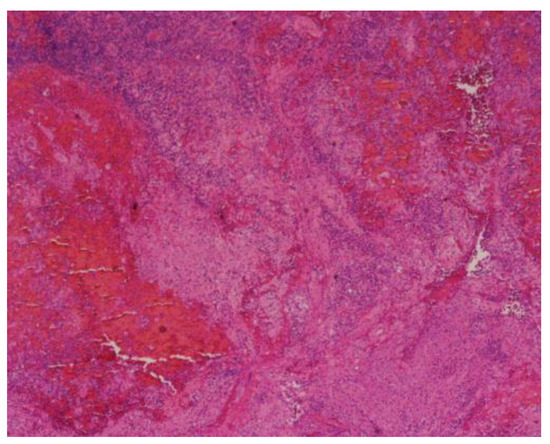

Introduction: Hypertension is occasionally associated with congenital hydronephrosis. Case report: The authors report a four-month-old boy with severe left congenital hydronephrosis and transient hypertension triggered by his first urinary tract infe...